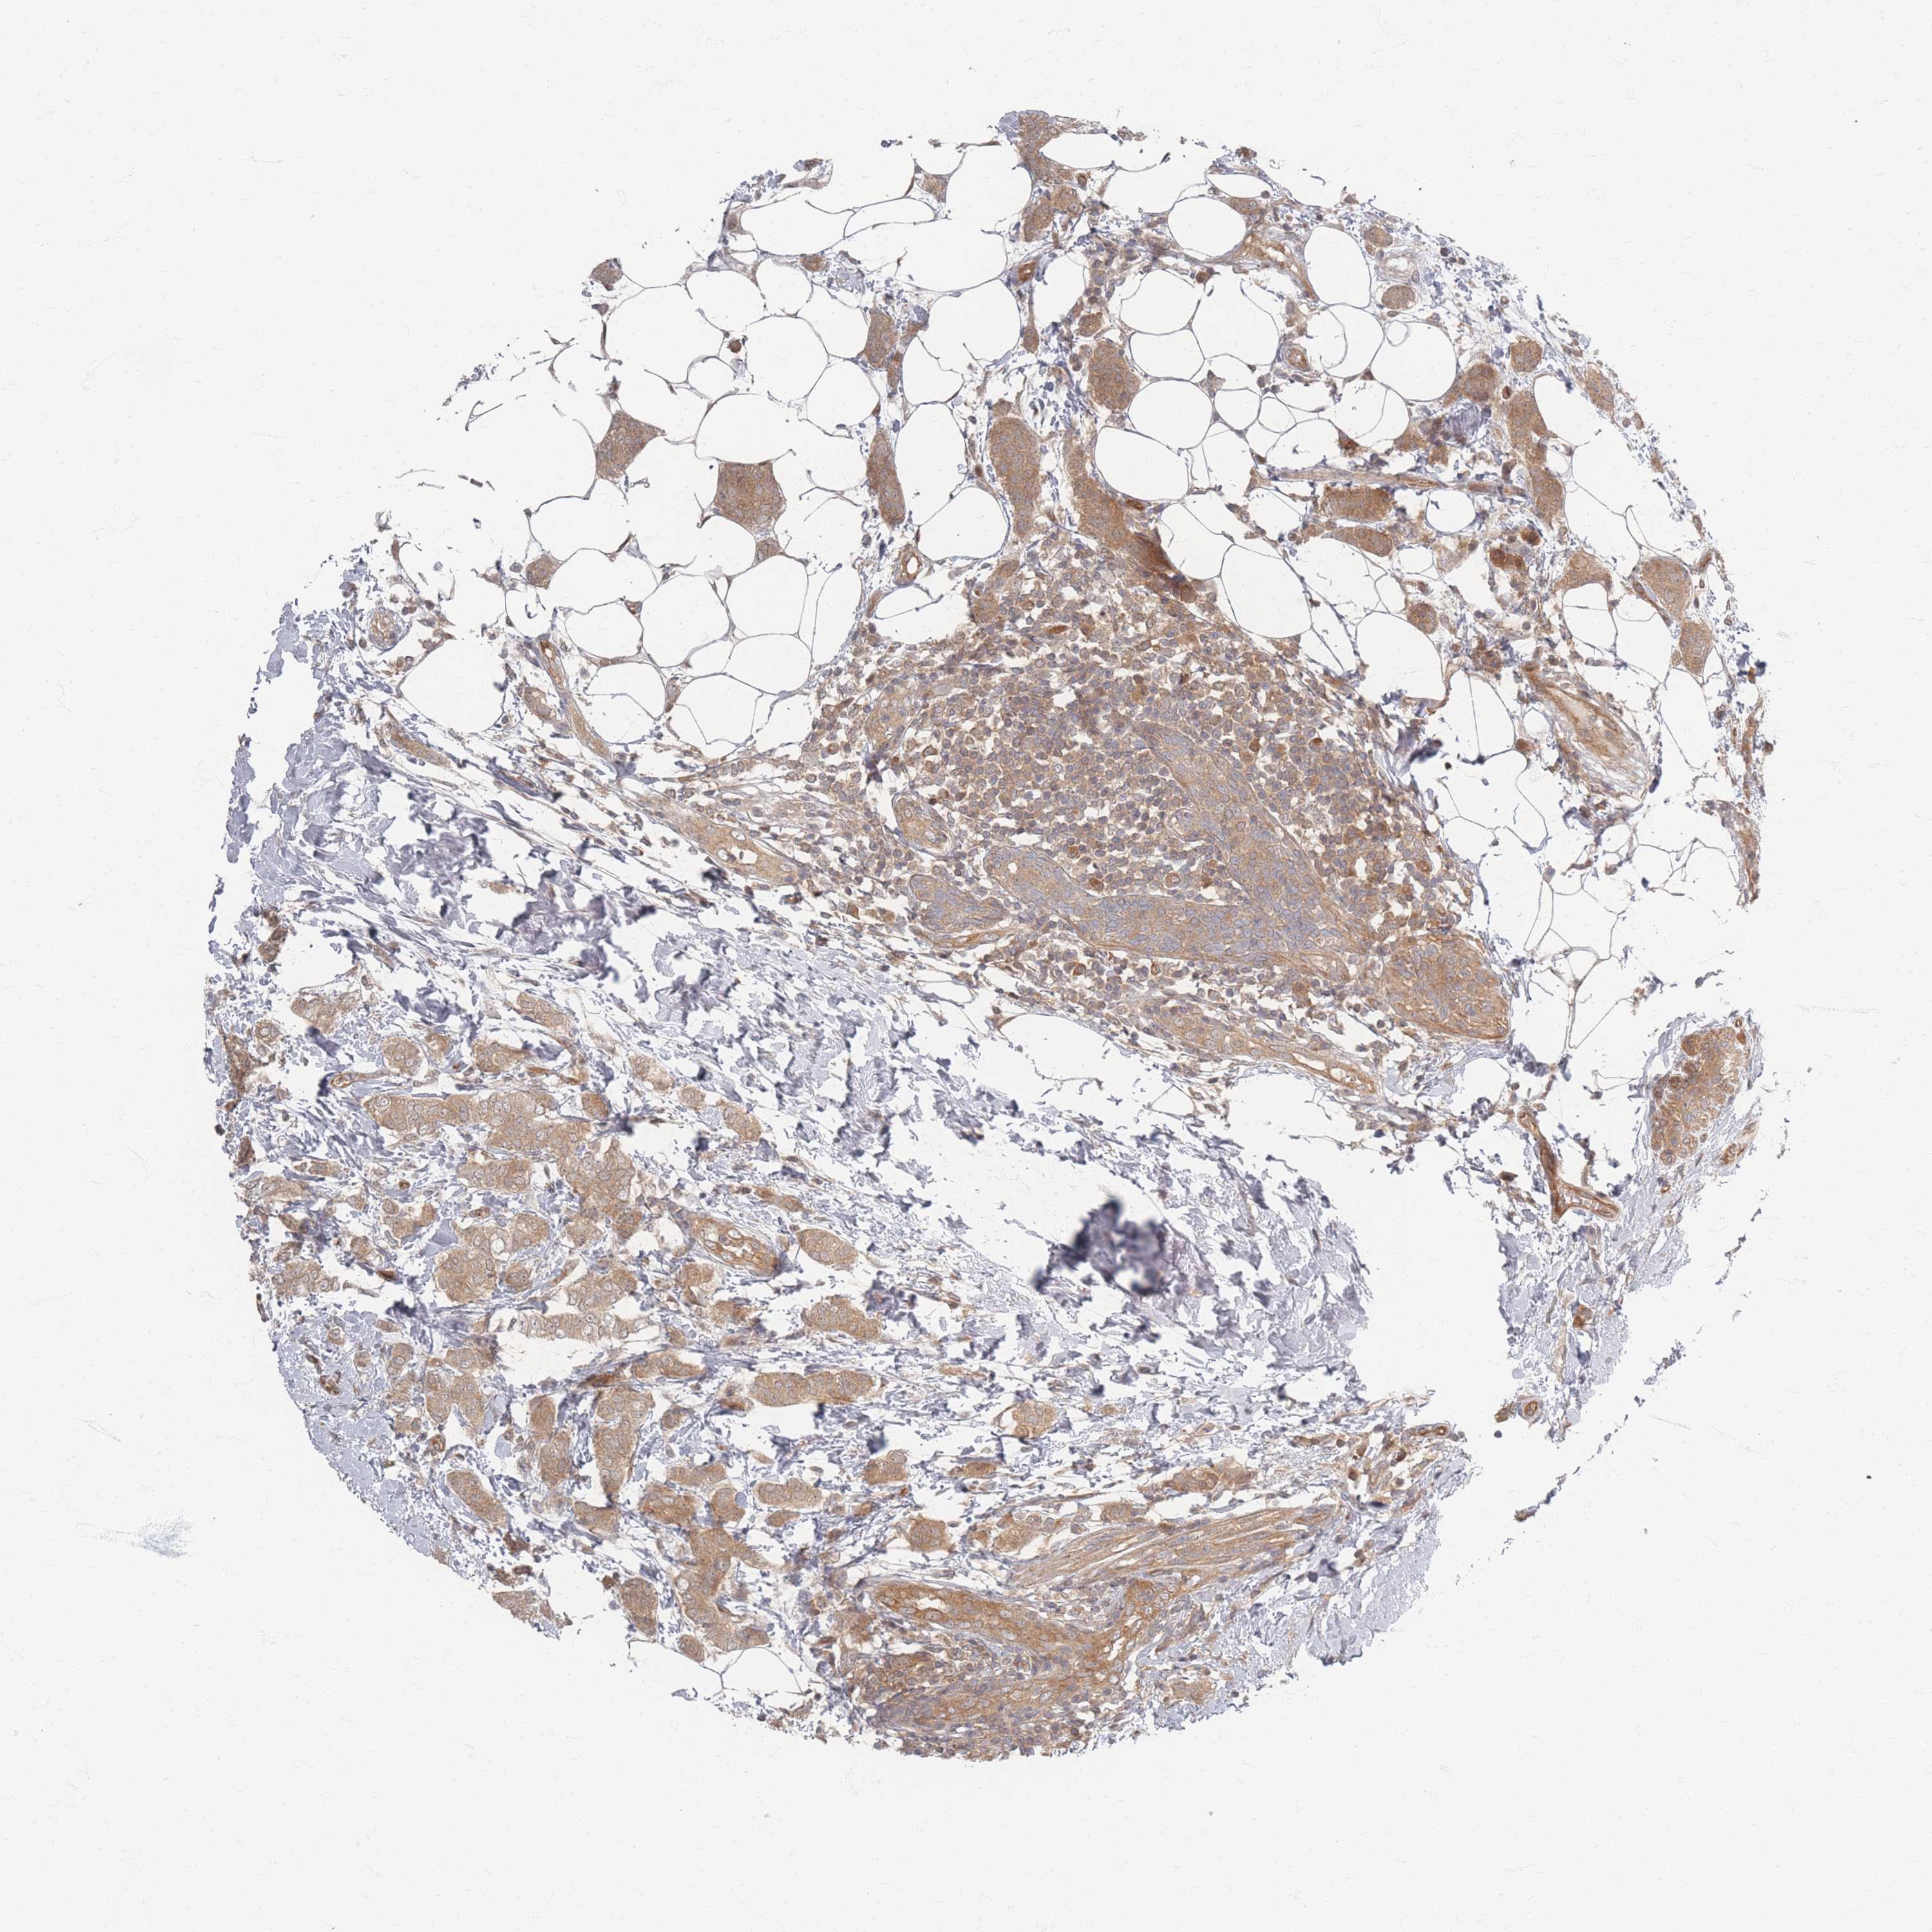

CANCER BREAST CANCER Show tissue menu

BRCA TCGA BRCA VALIDATION PROTEIN EXPRESSION